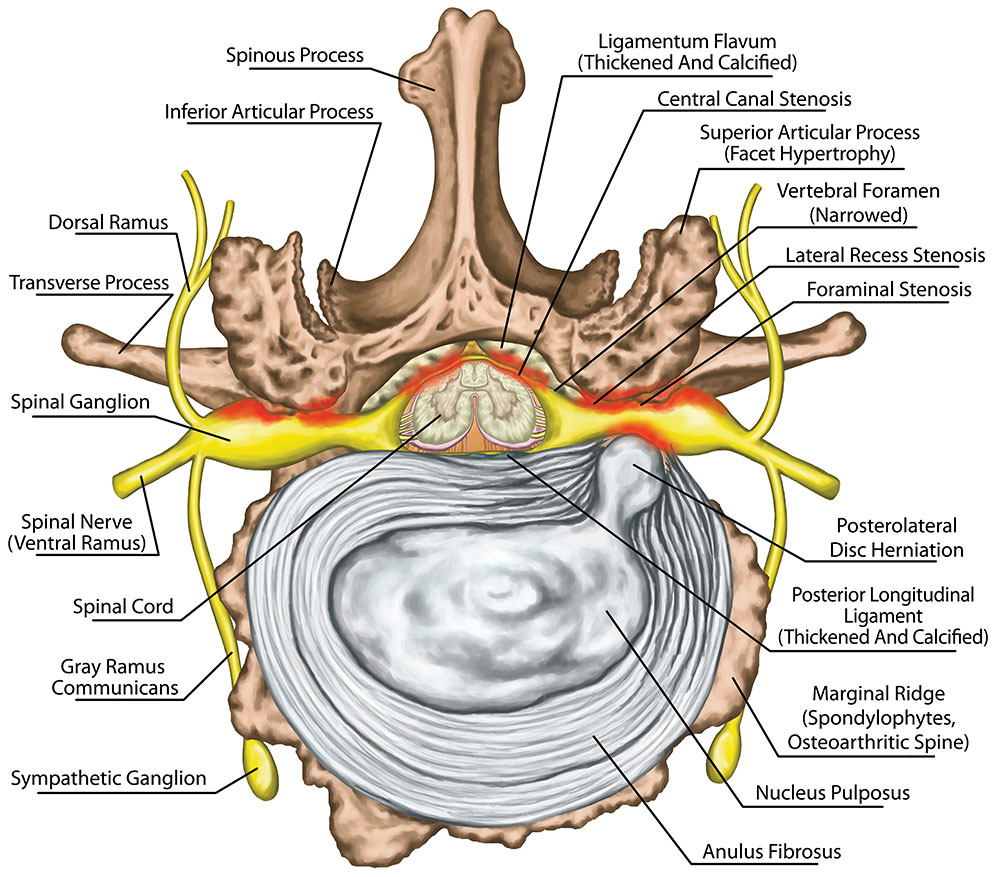

What are the different types of disc problems? | QI Spine

Bulging and Herniated Discs – Explained | Physical Health Care

What is the difference between a bulging disc and a herniated disc?

Herniated, Bulging or Slipped Discs – SOS Chiro

Sciatica, Spinal Stenosis, Bulging Disc & Other Disc Conditions